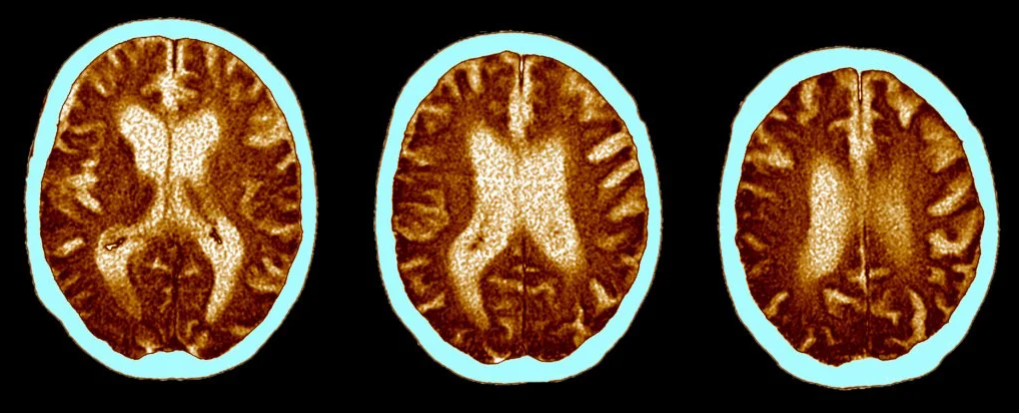

محققان دانشگاه کمبریج میگویند ابتلا به کرونای حاد میتواند روی تواناییهای شناختی و مغز افراد تاثیرگذار باشد تا جایی که اثر این بیماری معادل بیست سال پیر شدن مغز است.

در یک مطالعه جدید، محققان 46 بیمار مبتلا به کرونای حاد را با 460 شخص همسان – از نظر ویژگی جسمی و سنی – مقایسه کردند. آنها دریافتند تاثیر ویروس کرونا بر بدن شش ماه پس از ابتلا معادل با پیری 20 ساله یا از دست دادن 10 امتیاز هوشی است.

نتایج نشان داد کسانی که از ویروس کرونا جان سالم به در بردهاند، دقت کمتری داشتند و زمان پاسخدهی آنها نسبت به عموم مردم طولانیتر بود. این حالت مشابه با پیر شدن به اندازه 20 سال – بروز اثرات پیری بین 50 تا 70 سالگی – و یا از دست دادن 10 امتیاز IQ بود.